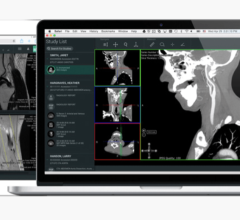

ViTALConnect software is a Web-enabled medical tool that allows physicians to use PCs or notebook computers to access interactive 2D, 3D and 4D advanced visualization. ViTALConnect software offers users access that is critical in today’s hospital environment. This solution enables users to review studies and perform advanced analysis from any where at any time. This communication tool includes collaboration capabilities that enable multiple physicians in different locations to confer while interacting with the same data in real-time.